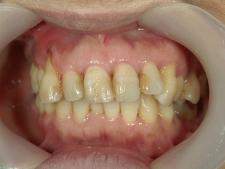

矯正歯科(全顎ワイヤー矯正)治療後

矯正歯科 治療後